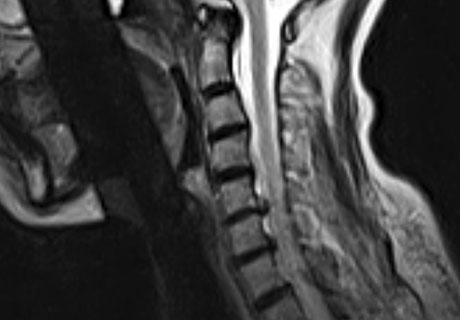

MRI로 본 환자 치료사례 (치료기간-입원치료 3주, 외래치료 1개월 / ABCDE 치료법)

모커리한방병원 목디스크 MRI 전/후 사진 이미지

모커리는 파열된 목디스크도 흡수될 수 있도록 도와주는 치료를 합니다.

※ After 사진은 6개월 후 촬영된 모습으로, 파열된 디스크가 깨끗하게 흡수된 것을 확인할 수 있습니다.